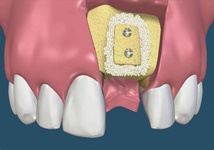

SonicWeld Rx

Novinkou v augmentačních metodách, kterou jako první v České republice používáme v našem zařízení je ultrazvuková metoda pomocí polylaktidové membrány - SonicWeld Rx®, kterou zavedl do implantologie v roce 2009 Dr. Dr. G.Iglhaut (Memmingen, Německo).

Jedná se o augmentační metodu při dostavbách kosti a defektech kosti horní a dolní čelisti.